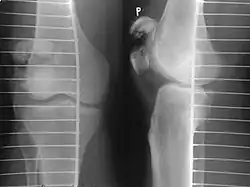

| A fracture of the patella seen on a lateral view | |

Transverse fracture of patella -